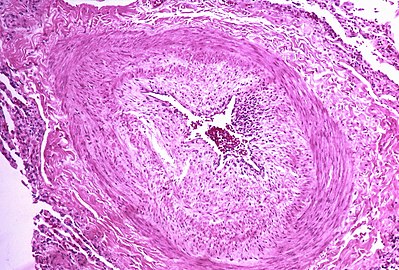

The pathogenesis of pulmonary arterial hypertension (WHO Group I) involves the narrowing of blood vessels connected to and within the lungs. This makes it harder for the heart to pump blood through the lungs, much as it is harder to make water flow through a narrow pipe as opposed to a wide one. Over time, the affected blood vessels become stiffer and thicker, in a process known as fibrosis. The mechanisms involved in this narrowing process include vasoconstriction, thrombosis, and vascular remodeling (excessive cellular proliferation, fibrosis, and reduced apoptosis/programmed cell death in the vessel walls, caused by inflammation, disordered metabolism and dysregulation of certain growth factors).[24][25] Over time, vascular remodeling causes the affected blood vessels to become progressively stiffer and thicker. This further increases the blood pressure within the lungs and impairs their blood flow. In common with other types of pulmonary hypertension, these changes result in an increased workload for the right side of the heart.[11][26] The right ventricle is normally part of a low pressure system, with systolic ventricular pressures that are lower than those that the left ventricle normally encounters. As such, the right ventricle cannot cope as well with higher pressures, and although right ventricular adaptations (hypertrophy and increased contractility of the heart muscle) initially help to preserve stroke volume, ultimately these compensatory mechanisms are insufficient; the right ventricular muscle cannot get enough oxygen to meet its needs and right heart failure follows.[11][25][26] As the blood flowing through the lungs decreases, the left side of the heart receives less blood. This blood may also carry less oxygen than normal. Therefore, it becomes harder and harder for the left side of the heart to pump to supply sufficient oxygen to the rest of the body, especially during physical activity.[27][28][19]

In PVOD (WHO Group 1'), pulmonary blood vessel narrowing occurs preferentially (though not exclusively) in post-capillary venous blood vessels.[29] PVOD shares several characteristics with PAH, but there are also some important differences, for example differences in prognosis and response to medical therapy.[citation needed]